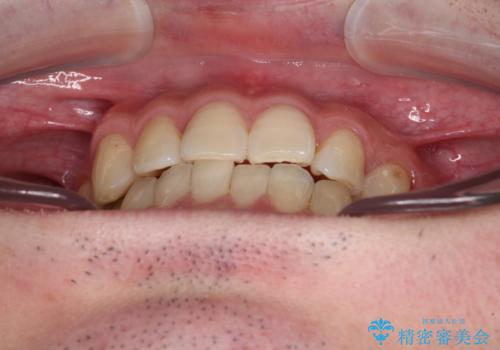

欠損のある歯列 インビザラインで整った歯並びに

- デコボコした前歯をセラミックできれいに揃えたいとのことで来院された患者様です。

歯を削って整えることは簡単ですが、健全な歯を削って後悔してからでは遅いため、矯正治療を提案しました。

はじめは矯正治療の期間が長いことに悩んでいらっしゃいましたが、ある程度整えば満足するだろうとのことで、インビザラインにて矯正治療を行うこととしました。

左上の犬歯が欠損しているため、正中の位置や奥歯の咬み合わせが理想的にならない点を了承していただきました。